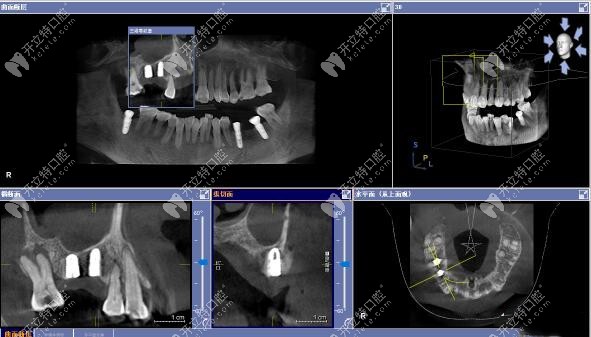

3D數(shù)字化導(dǎo)板上頜竇區(qū)種植案例

▲術(shù)后CT顯示:上頜15號(hào)、16號(hào)缺牙位置的植體,均已達(dá)到了預(yù)期位置。

用3D數(shù)字化導(dǎo)板技術(shù)做上頜區(qū)種植牙,更微創(chuàng)只有3MM左右、無(wú)需縫合、更精準(zhǔn)、更安全,大大降低了傳統(tǒng)種植手術(shù)中不可預(yù)知的風(fēng)險(xiǎn)。